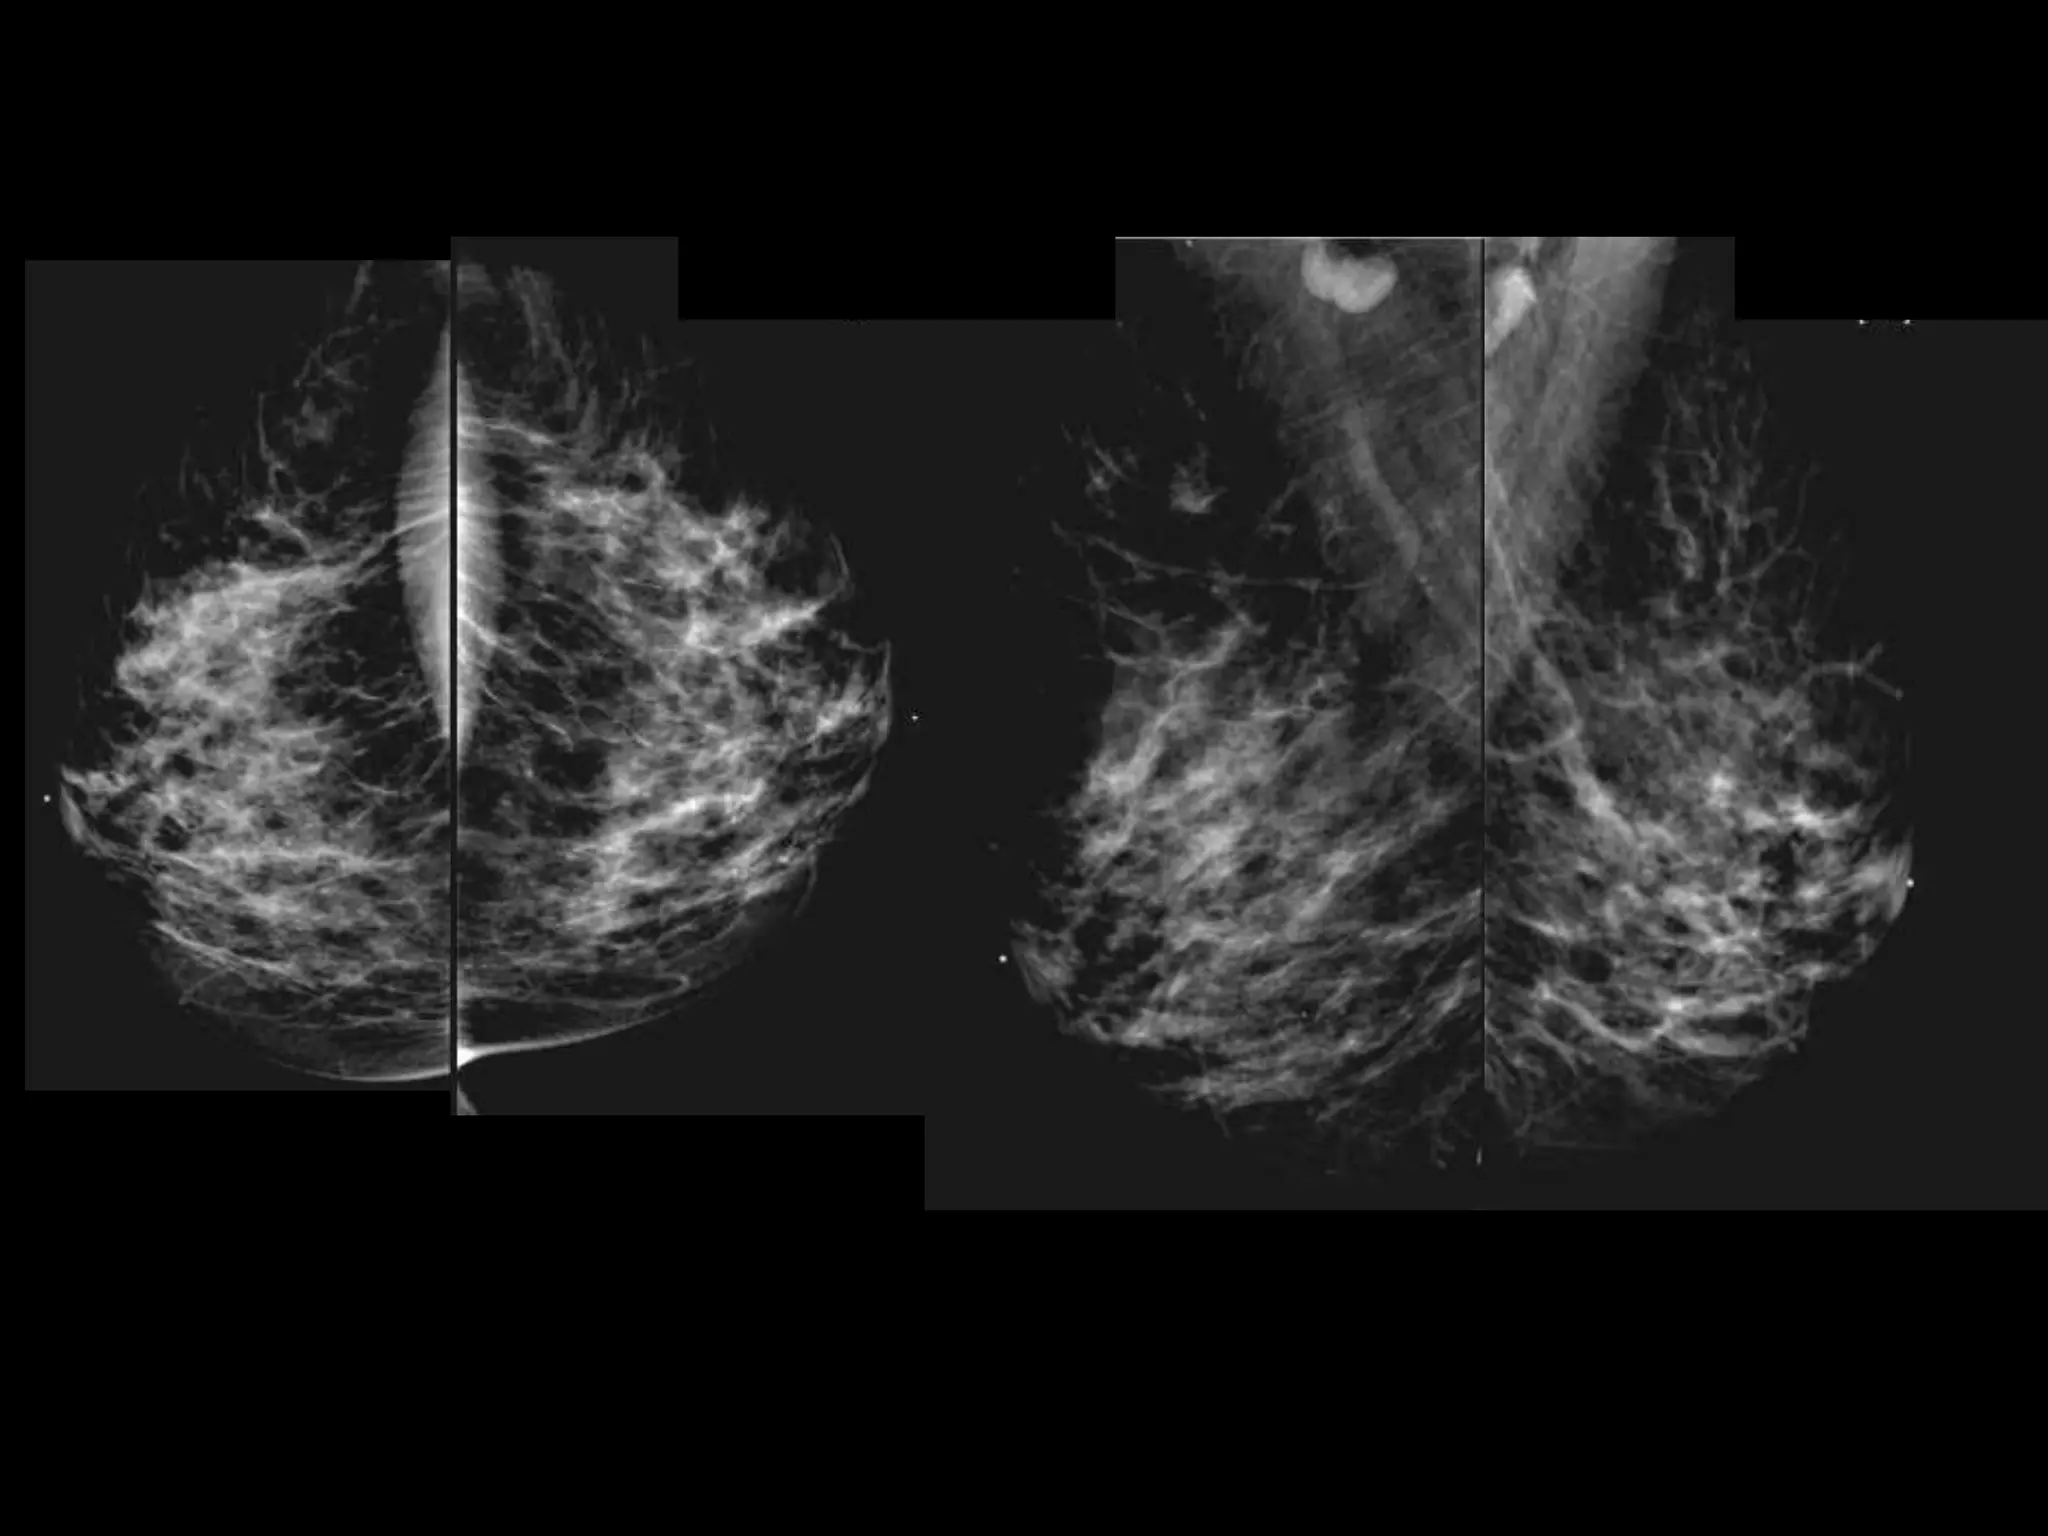

Current Bilateral Mammogram

RCC      LCC             RMLO       LMLO

Current and Comparison Left Breast MGs

4 YRS PRIOR               CURRENT              4 YRS PRIOR

HISTORY โ€ข 65 yofemale โ€ข Presents from OSH with worsening โ€žleft breast swellingโ€Ÿ for 8-9 months โ€ข New 1 month history of โ€žchange in left nippleโ€Ÿ

Current and ComparisonLeft Breast MGs 4 YRS PRIOR CURRENT 4 YRS PRIOR

US retroareolar region US Left upper outer breast

Invasive Lobular Carcinoma โ€ข10-15% of all invasive breast ca โ€ข Sensitivity of MG 57-81% โ€“ Mass most common โ€“ usually spiculated (44- 65%) โ€“ Distortion 10-34% โ€“ Asymmetry 1-14% โ€ข Much less freq assoc with calcs than IDC โ€ข Sensitivity of US 68-98% โ€“ Spiculated mass โ€“ Shadowing Lopez et al. Radiographics 2009; 29:165.

Invasive Lobular Carcinoma โ€ขSensitivity of MRI up to 95% โ€“ Changes in clinical management up to 50% โ€“ Changes in surgical management up to 28% โ€ข Kinetics โ€“ progressive more typical than washout Lopez et al. Radiographics 2009; 29:165.